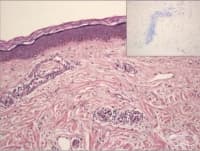

Гангрена

Гангрената е вид некроза, причинена от критично недостатъчно кръвоснабдяване на тъканите. Това потен...